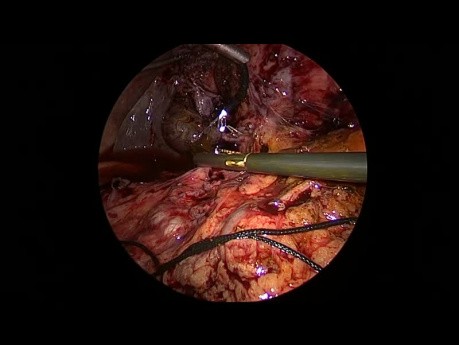

Cœlioscopie diagnostique du conduit cholédoque...

C'est le cas vidéo de l'exploration du conduit cholédoque par une cholédochotomie à l'aide des instruments standards de 3 mm et un cholédochoscope flexible de 3 mm.